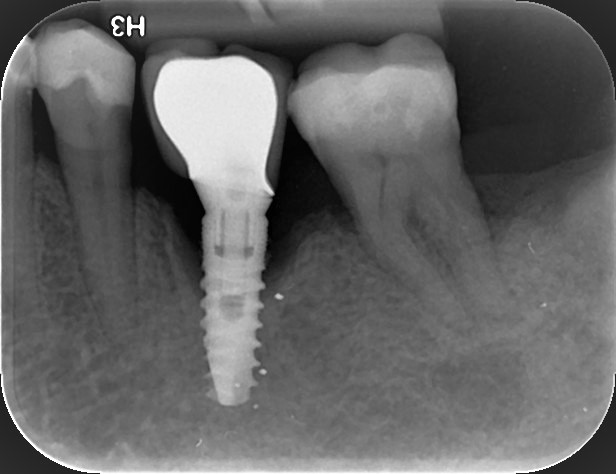

Η οπισθοφατνιακή ακτινογραφία λαμβάνεται με την τοποθέτηση του ακτινογραφικού πλακιδίου εσωτερικά των δοντιών (προς την πλευρά της γλώσσας ή του ουρανίσκου) και παράλληλα με αυτά. Χρησιμοποιείται ειδικός συγκρατητήρας του φιλμ, τον οποίο δαγκώνει ο εξεταζόμενος. Με αυτή απεικονίζονται ένα ή περισσότερα δόντια (τόσο η μύλη, όσο και η ρίζα αυτών), καθώς και τμήμα του φατνιακού οστού που περιβάλλει τις ρίζες των δοντιών. Αποτελεί την πιο απλή οδοντιατρική ακτινογραφική απεικόνιση. Χρησιμοποιούνται τρία μεγέθη φιλμ ή πλακιδίου ανάλογα με την περιοχή που θέλουμε να απεικονιστεί, το μέγεθος του στόματος του εξεταζόμενου και την ηλικία του. Η λήψη της είναι γρήγορη (διαρκεί λίγα δευτερόλεπτα) και ανώδυνη.

• την ανίχνευση οδοντικών τερηδόνων, τον καθορισμό της έκτασης και του βάθους τους και της σχέσης τους με τον πολφό του δοντιού

• τη μελέτη των ριζών των δοντιών (αριθμός, μορφολογία και πιθανή κάμψη αυτών, ύπαρξη απορρόφησης ή κατάγματος)

• τη μελέτη του αριθμού, της μορφολογίας, του εύρους και της πορείας των ριζικών σωλήνων εντός των ριζών

• τη μελέτη των σκληρών ιστών του περιοδοντίου, δηλαδή του φατνιακού οστού που περιβάλλει και στηρίζει το δόντι και του περιοδοντικού συνδέσμου. Σε περίπτωση περιοδοντικής νόσου, καθορίζεται η εντόπιση, ο βαθμός και η φύση (οριζόντια, γωνιώδης) της απορρόφησης του φατνιακού οστού

• τη μελέτη του φατνιακού οστού της περιακρορριζικής περιοχής του δοντιού για ύπαρξη παθολογικών εξεργασιών (απόστημα, κοκκίωμα, κύστη κ.λ.π.)

• την ανίχνευση κατάγματος των δοντιών.